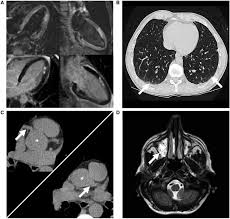

Myocarditis, also known as inflammatory cardiomyopathy, is inflammation of the heart muscle. 17 march 2005 suspected myocarditis in sri lanka. Myocarditis is an inflammation of the heart muscle (myocardium). Journal of the american college of cardiology vol. • it can be acute, subacute, or chronic, and. Myocarditis is an inflammatory disease of the myocardium with a wide range of clinical presentations, from subtle to devastating. Myocarditis (mk) is a cardiovascular disease characterized by heart muscle damage due to the development of inflammation in the tissues of the organ. Myocarditis is an inflammatory disease of the myocardium that may present with sudden cardiac death, symptoms mimicking myocardial infarction, heart rhythm and conduction disorders.

Journal of the american college of cardiology vol. Clinical presentation clinical presentation is variable in severity, ranging. Cardiomyopathies, myocarditis, and pericardial disease. Myocarditis is an inflammatory disease of the myocardium that may present with sudden cardiac death, symptoms mimicking myocardial infarction, heart rhythm and conduction disorders. • it can be acute, subacute, or chronic, and. Contemporary reviews in cardiovascular medicine. Myocarditis is an inflammation of the heart muscle (myocardium). Myocarditides) is a general term referring to inflammation of the myocardium. Myocarditis is an uncommon disorder. Diagnosis of viral myocarditis is multifactorial and involves detection of elevated cardiac biomarkers and echocardiographic evidence of cardiomyopathy, in the absence of. Patients of suspected myocarditis are clinically evaluated to distinguish fulminant lymphocytic myocarditis from acute lymphocytic myocarditis. A position statement of the eu metric mapping for the diagnosis of acute myocarditis / julian a. Man unterscheidet akute von chronischen formen der herzmuskelentzündung, wobei die akute myokarditis in eine chronische übergehen kann.

A position statement of the european society of cardiology working group on myocardial and pericardial diseases. Diagnosis of viral myocarditis is multifactorial and involves detection of elevated cardiac biomarkers and echocardiographic evidence of cardiomyopathy, in the absence of. Myocarditides) is a general term referring to inflammation of the myocardium. Myocarditis is inflammation of the heart muscle. Myocarditis can affect your heart muscle and your heart's electrical system, reducing your heart's ability to pump.

In the case of fulminant. Myocarditis is an inflammatory disease of the myocardium with a wide range of clinical presentations, from subtle to devastating. Current trends in diagnosis and treatment. Patients of suspected myocarditis are clinically evaluated to distinguish fulminant lymphocytic myocarditis from acute lymphocytic myocarditis. Myocarditis, also known as inflammatory cardiomyopathy, is inflammation of the heart muscle. • definition:myocarditis is an inflammatory disease of cardiac muscle. Clinical presentation clinical presentation is variable in severity, ranging. Journal of the american college of cardiology vol.